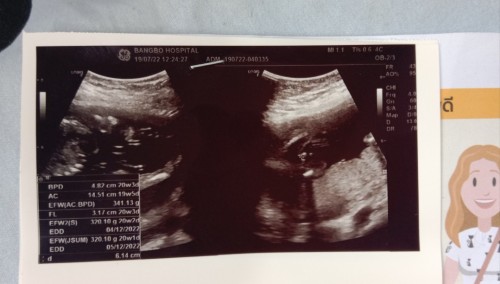

20w2d น้ำหนัก320.10g น้อยไปไหมคะแม่ๆ พึ่งไปซาวด์มาเมื่อวานค่ะ คนที่บ้านเราบอกว่าน้อยไป เคลียดเลยค่ะ😔#ท้องแรกคะ #ขอคำแนะนำหน่อยค่ะ